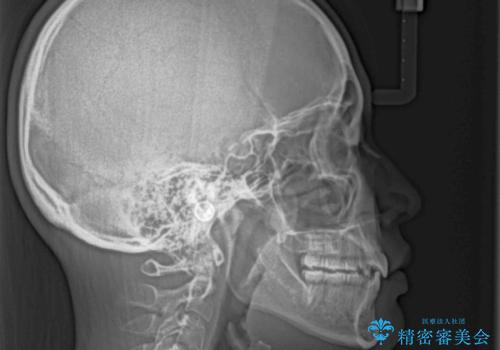

ワイヤー装置の抜歯矯正で横顔のシルエットをすっきりと

上下ともに歯列が前方に突出していたため、上下左右の第一小臼歯4本を抜去し、ワイヤー装置による矯正治療を行うこととしました。

上下左右4本抜歯する場合には、通常2年から2年半ほどの期間を要しますが、舌のトレーニングをしっかりと行っていただいたことで、1年9ヶ月で終了することができました。